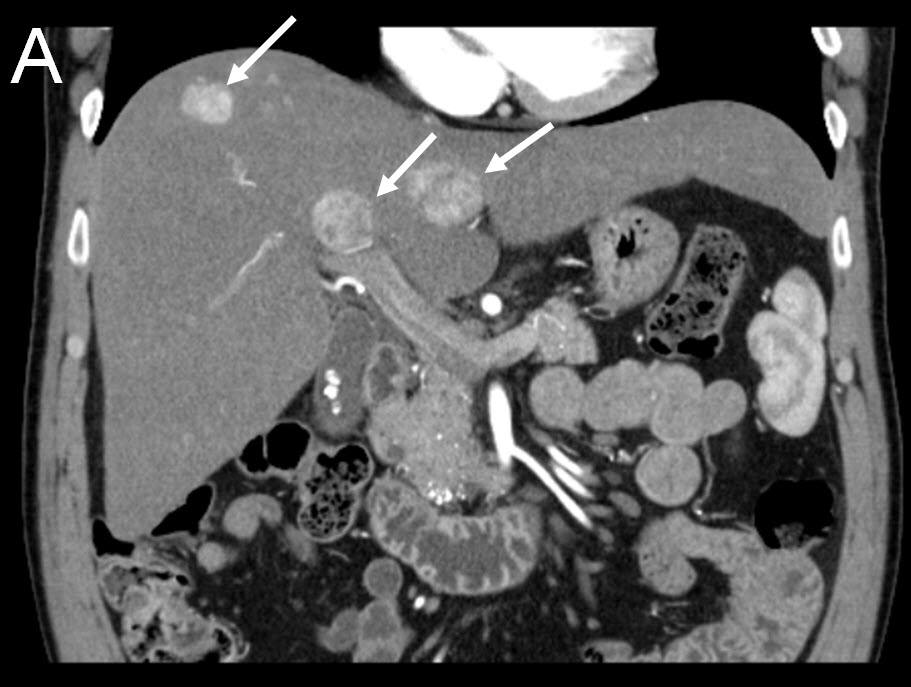

| (A) Coronal CT-scan of patient with multiple liver tumors |